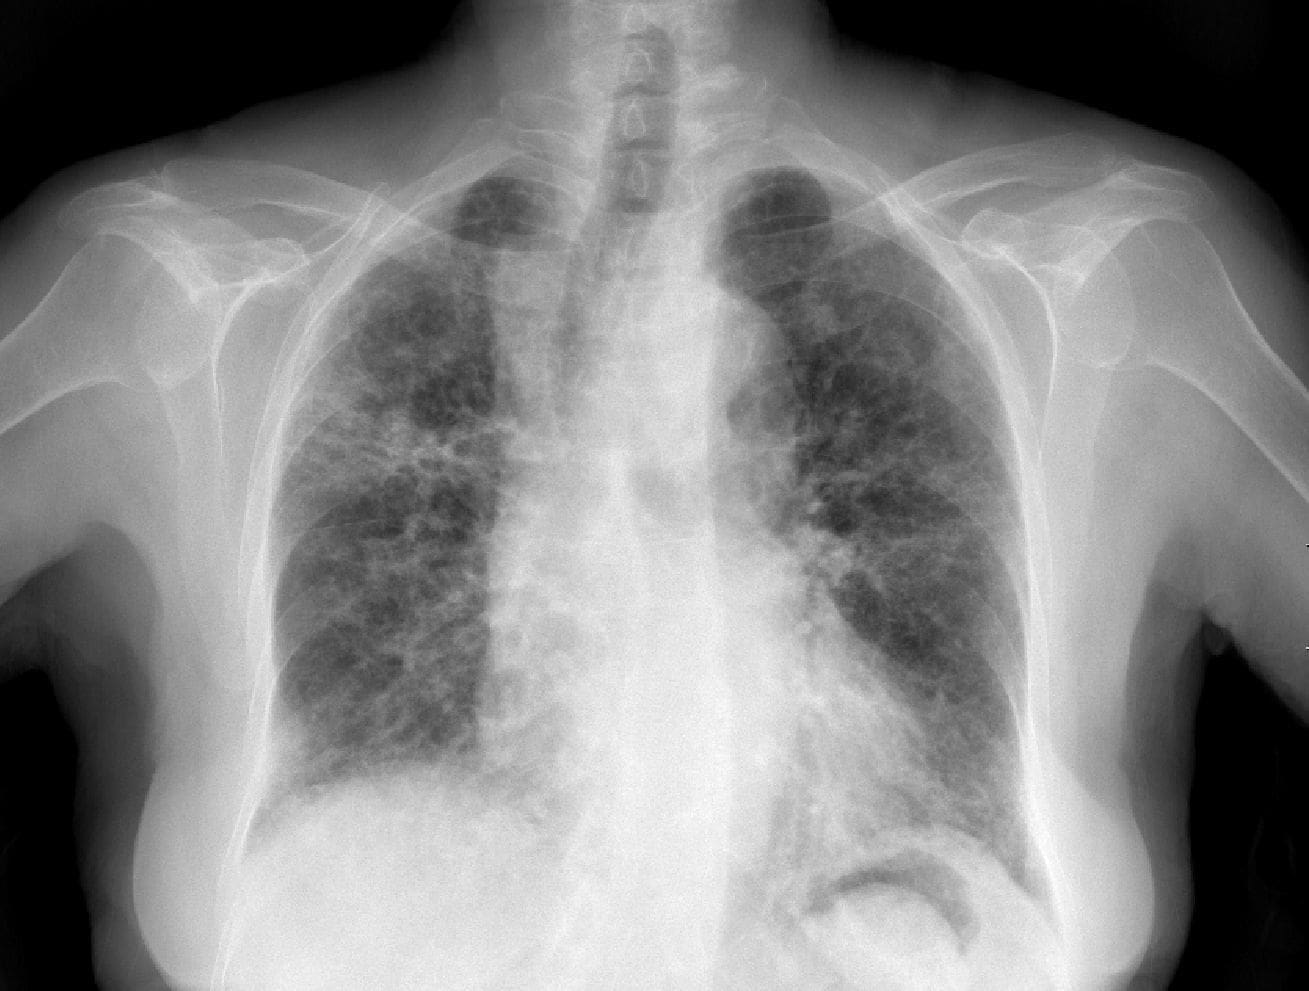

La radiografía de tórax fue anormal en todos los pacientes, presentando zonas de ocupación alveolar, cavitaciones, lesiones compatibles con bronquiectasias y una imagen sugestiva de micetoma. La TAC fue realizada en la mitad de los pacientes confirmando lesiones cavitarias, ocupación alveolar y bronquiectasias.

Figura 3. Paciente de sexo masculino, de 50 años, con hemoptisis masiva por TBC activa en lóbulo superior derecho. (a) Arteriografía bronquial derecha, muestra dilatación y tortuosidad de las ramas bronquiales, como signo indirecto de sangrado. (b) Control de embolización con partículas de gelfoam + alcohol absoluto, con oclusión total de la arteria y remisión de la hemoptisis.